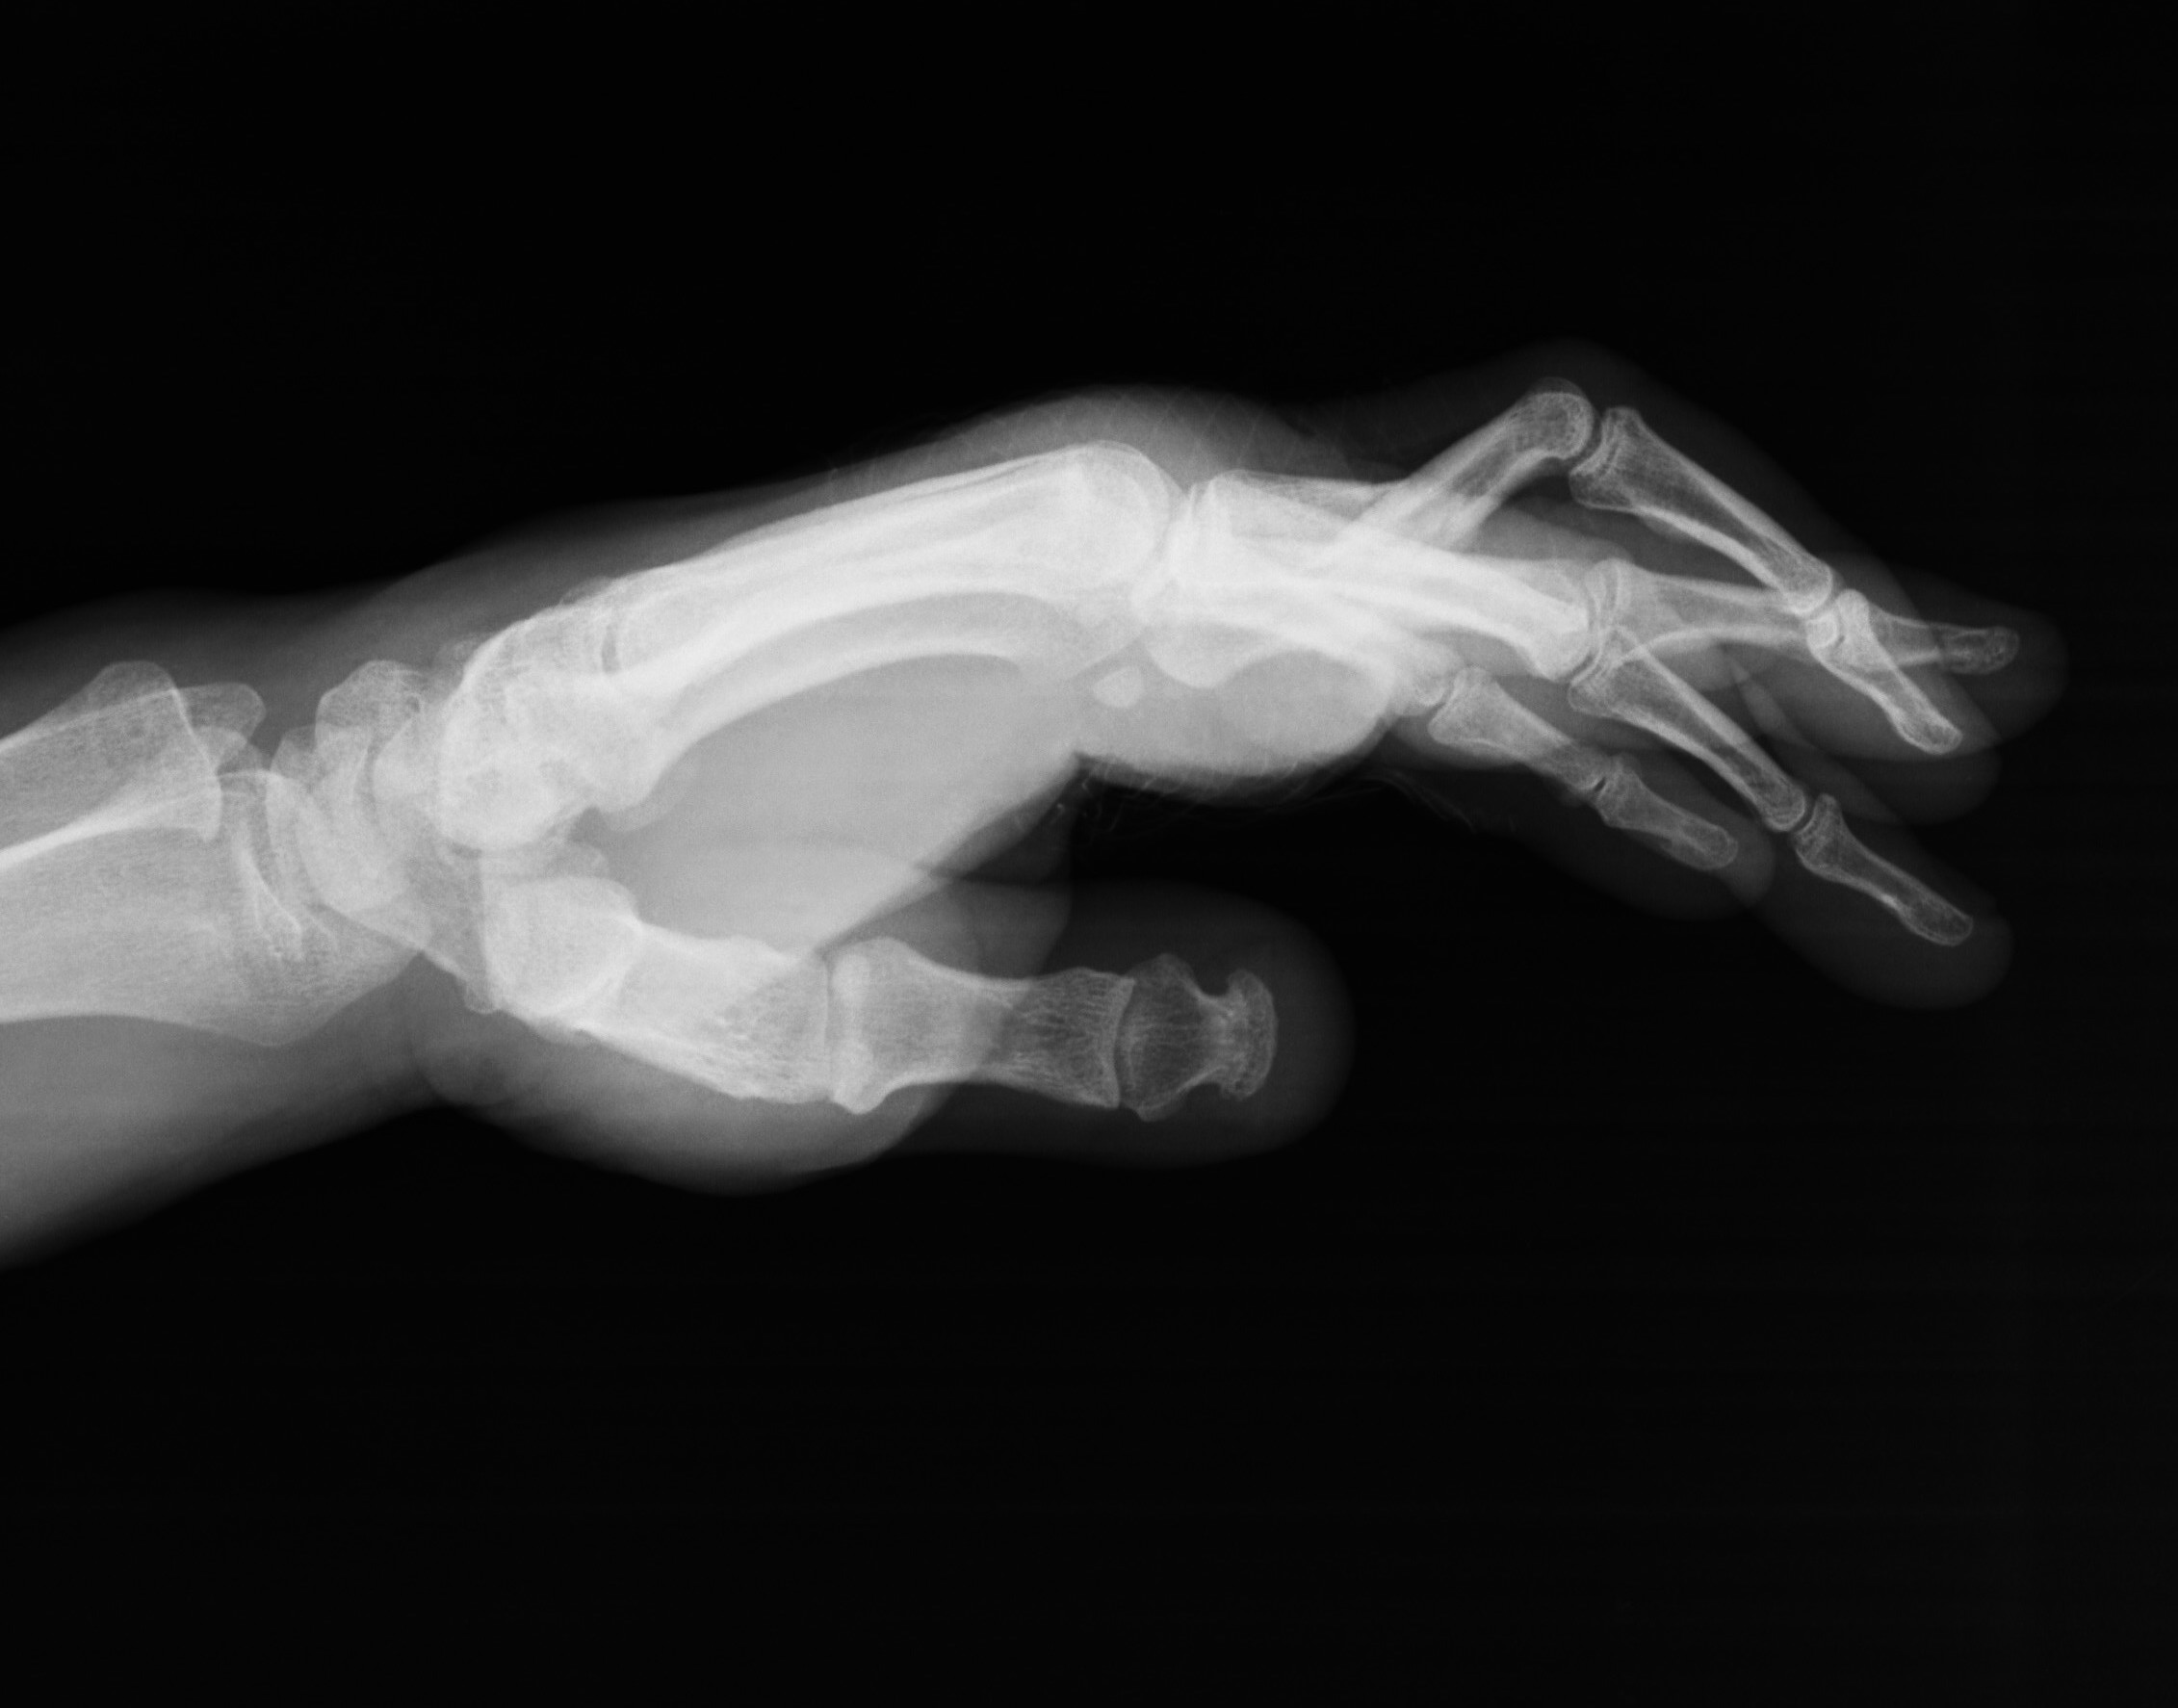

Fracturas del escafoides: (Figura 5) En boxeo son poco frecuentes, pero posibles tras impactos con el puño desalineado. El diagnóstico puede retrasarse y derivar en necrosis avascular.

Figura 5 - Mecanismo de producción de las fracturas de escafoides en el boxeo.